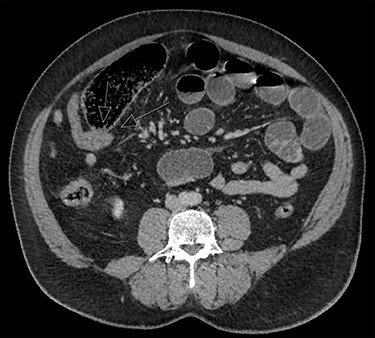

Case 2 is a 56-year-old male, with a virgin abdomen, who had 2 days of crampy abdominal pain, vomiting and obstipation. He was haemodynamically normal and afebrile. He had a distended abdomen with generalized tenderness. Blood tests showed an elevated lactate of 3 and WCC of 11.7 × 109. CT demonstrated distal SBO, with distension of small bowel up to 6 cm (Fig. 3). He underwent a diagnostic laparoscopy with an identification of MD at the transition point, subsequently exteriorized through a mini-laparotomy (Fig. 2). The apex of the MD was tethered to the mesentery through a band containing the diverticular blood supply. Small bowel resection and anastomosis was performed. Histopathology showed MD with acute inflammation, haemorrhage and necrosis, and no ectopic tissue.

The diagnosis of MD as the cause of SBO is often not made until the operation. CT is very accurate in identifying an obstruction, although it has poor sensitivity and specificity in detecting MD. For instance, pre-operative diagnosis with CT was made in only 50% in a recent case series of MD causing SBO. Radiological features suggesting this diagnosis include dilated small bowel loops with a transition point at or near midline, presence of a blind-ending tubular pouching of the distal ileum located at the terminal branch of the SMA with or without inflammation or enterolith. Relevant negative findings include a normal appendix and no previous surgery [7].